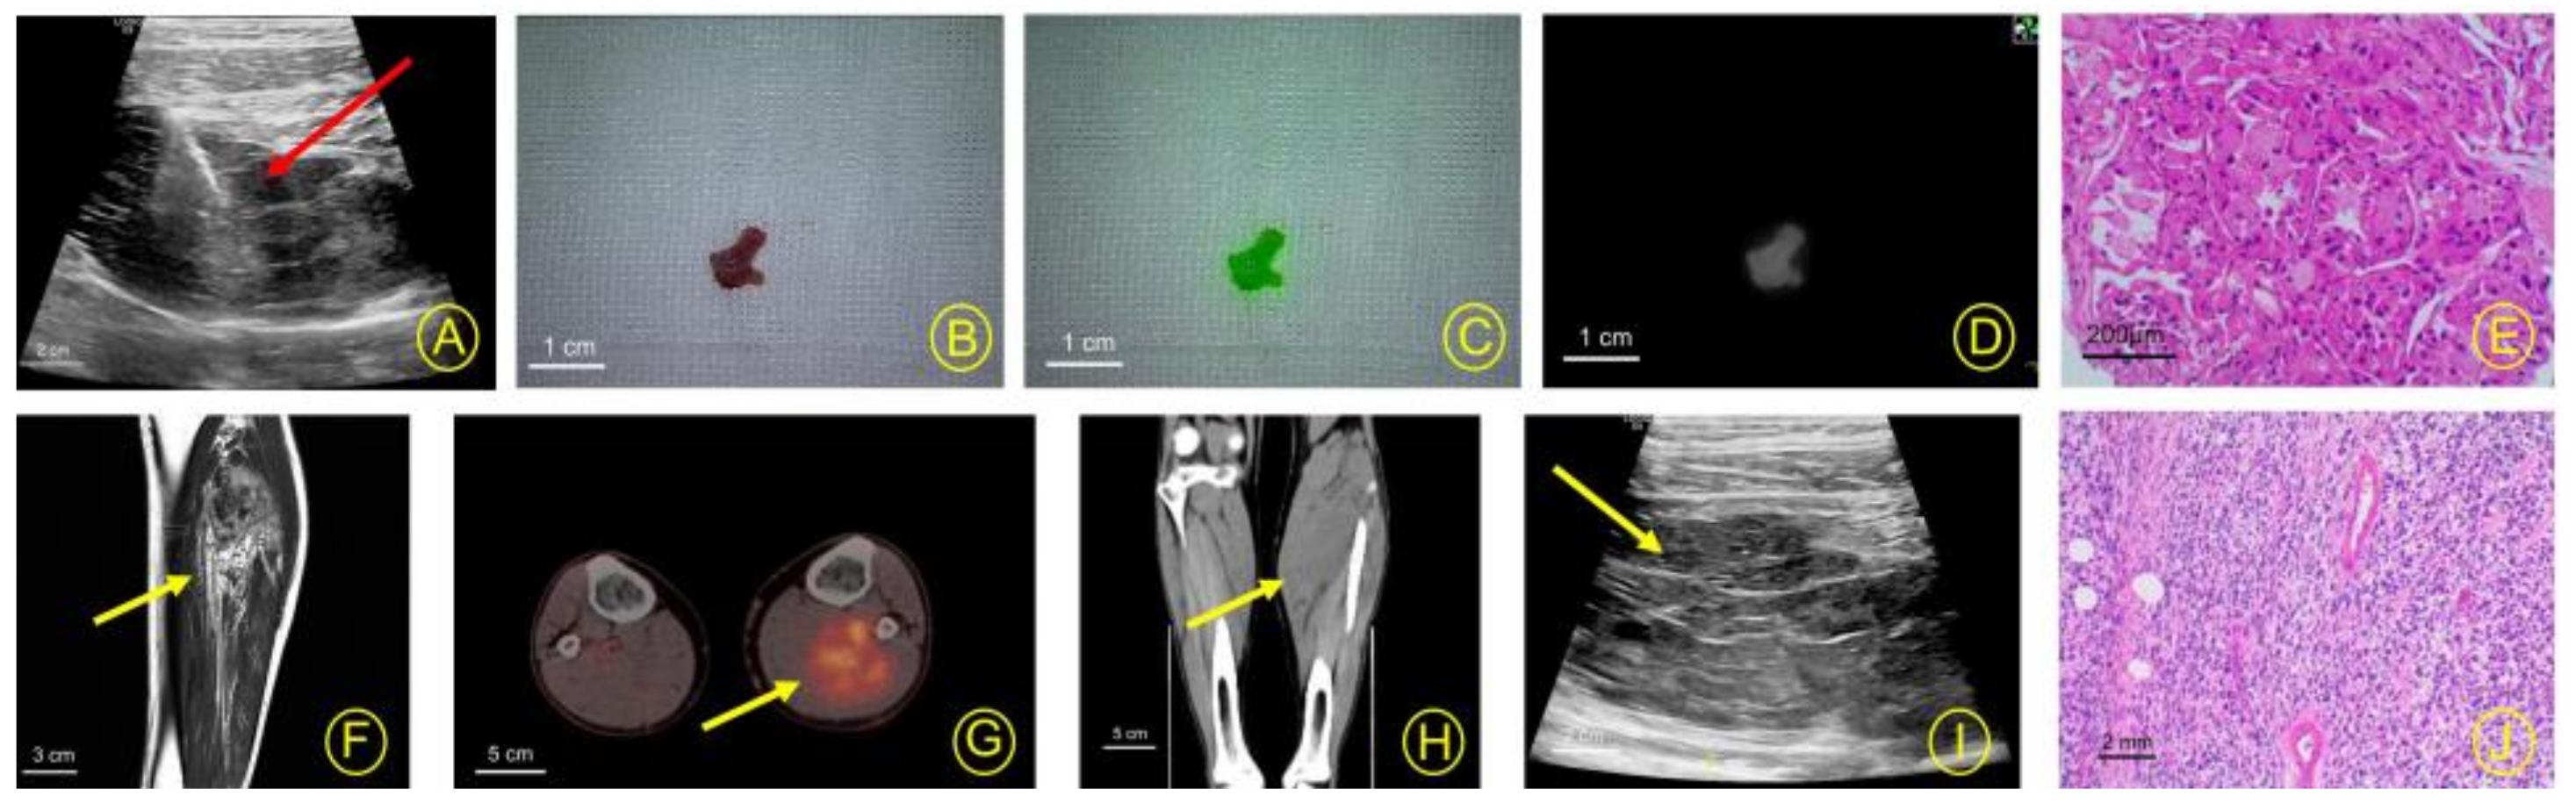

2.2. Core Biopsy Guided by Imaging Equipment

2.3.1. Control Group

2.3.2. Test Group

2.4. Investigational Drug

2.5. Experimental Equipment

2.5.1. Photo Device

2.5.2. Biopsy Device